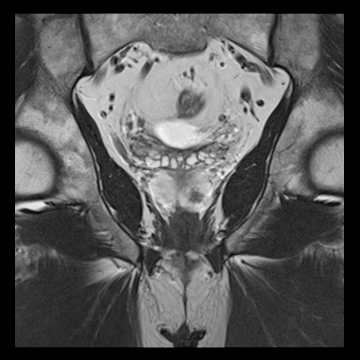

前立腺

高分解能T2

T2

RESOLVE, b=800

and ADC map,